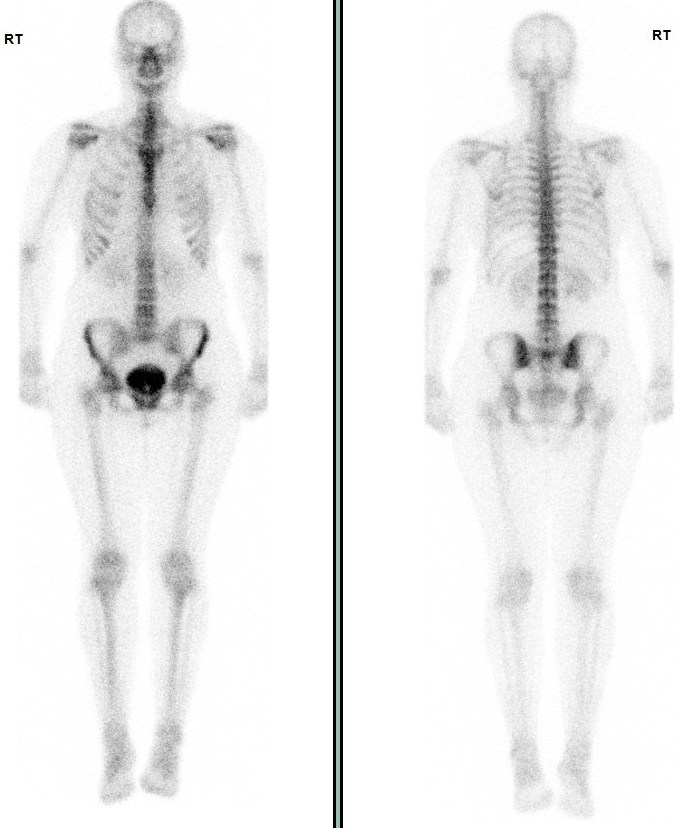

Nuclear Medicine - Bone Scan

A bone scan is a type of nuclear radiology procedure. This means that a tiny amount of a radioactive substance is used during the procedure to assist in the examination of the bones. The radioactive substance, called a radionuclide or tracer, will collect within the bone tissue at spots of abnormal physical and chemical change.

The radionuclide emits a type of radiation, called gamma radiation. The gamma radiation is detected by a scanner, which processes the information into a picture of the bones.

The areas where the radionuclide collects are called "hot spots" and may indicate the presence of conditions such as arthritis, malignant bone tumours, metastatic bone cancer, bone infections, bone trauma not seen on ordinary x-rays and other conditions of the bone.